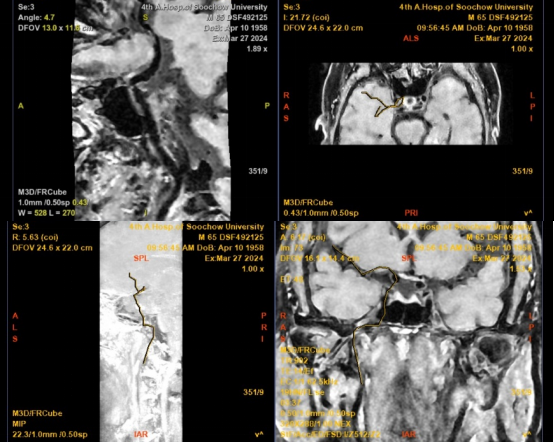

患者为一名65岁男性,3月16日突发左侧肢体活动障碍,次日症状加重,并出现反应迟钝、言语不清、口角歪斜等新发症状后转至苏大附四院继续治疗。入院后CTA(CT血管造影术)检查提示右侧大脑中动脉水平段(R-M1)管腔完全闭塞,远段分支稀疏;CTP(脑灌注检查)则提示右侧额顶颞叶缺血性灌注异常;头颅MRI(核磁共振成像)见右侧岛叶、颞叶、右侧脑室旁及放射冠区急性脑梗死。综合检查结果,考虑到患者发病时间较长,与家属商议后予以强化内科治疗。

MRI:右侧岛叶、颞叶、右侧脑室旁及放射冠区急性脑梗死

CTA+CTP:右侧大脑中动脉水平段(R-M1)管腔完全闭塞;右侧额顶颞叶缺血性灌注异常

MRI平扫+增强:右侧大脑中动脉M1段远端不稳定斑块并管腔重度狭窄